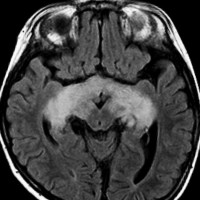

化学療法が有効なのは,上の画像のようにガドリニウム増強で強く増強されるタイプです,またT2強調画像で強い高信号になるものほど化学療法が有効です,要するに毛様粘液性星細胞腫の要素に化学療法が有効であるということです

この毛様細胞性星細胞腫はガドリニウムでほとんど増強されません(右側のMRI)から,化学療法を行っても小さくなりませんので,手術摘出する必要があります,実際に視床下部から発生したもの視交叉が犯されておらず,手術亜全摘出できました